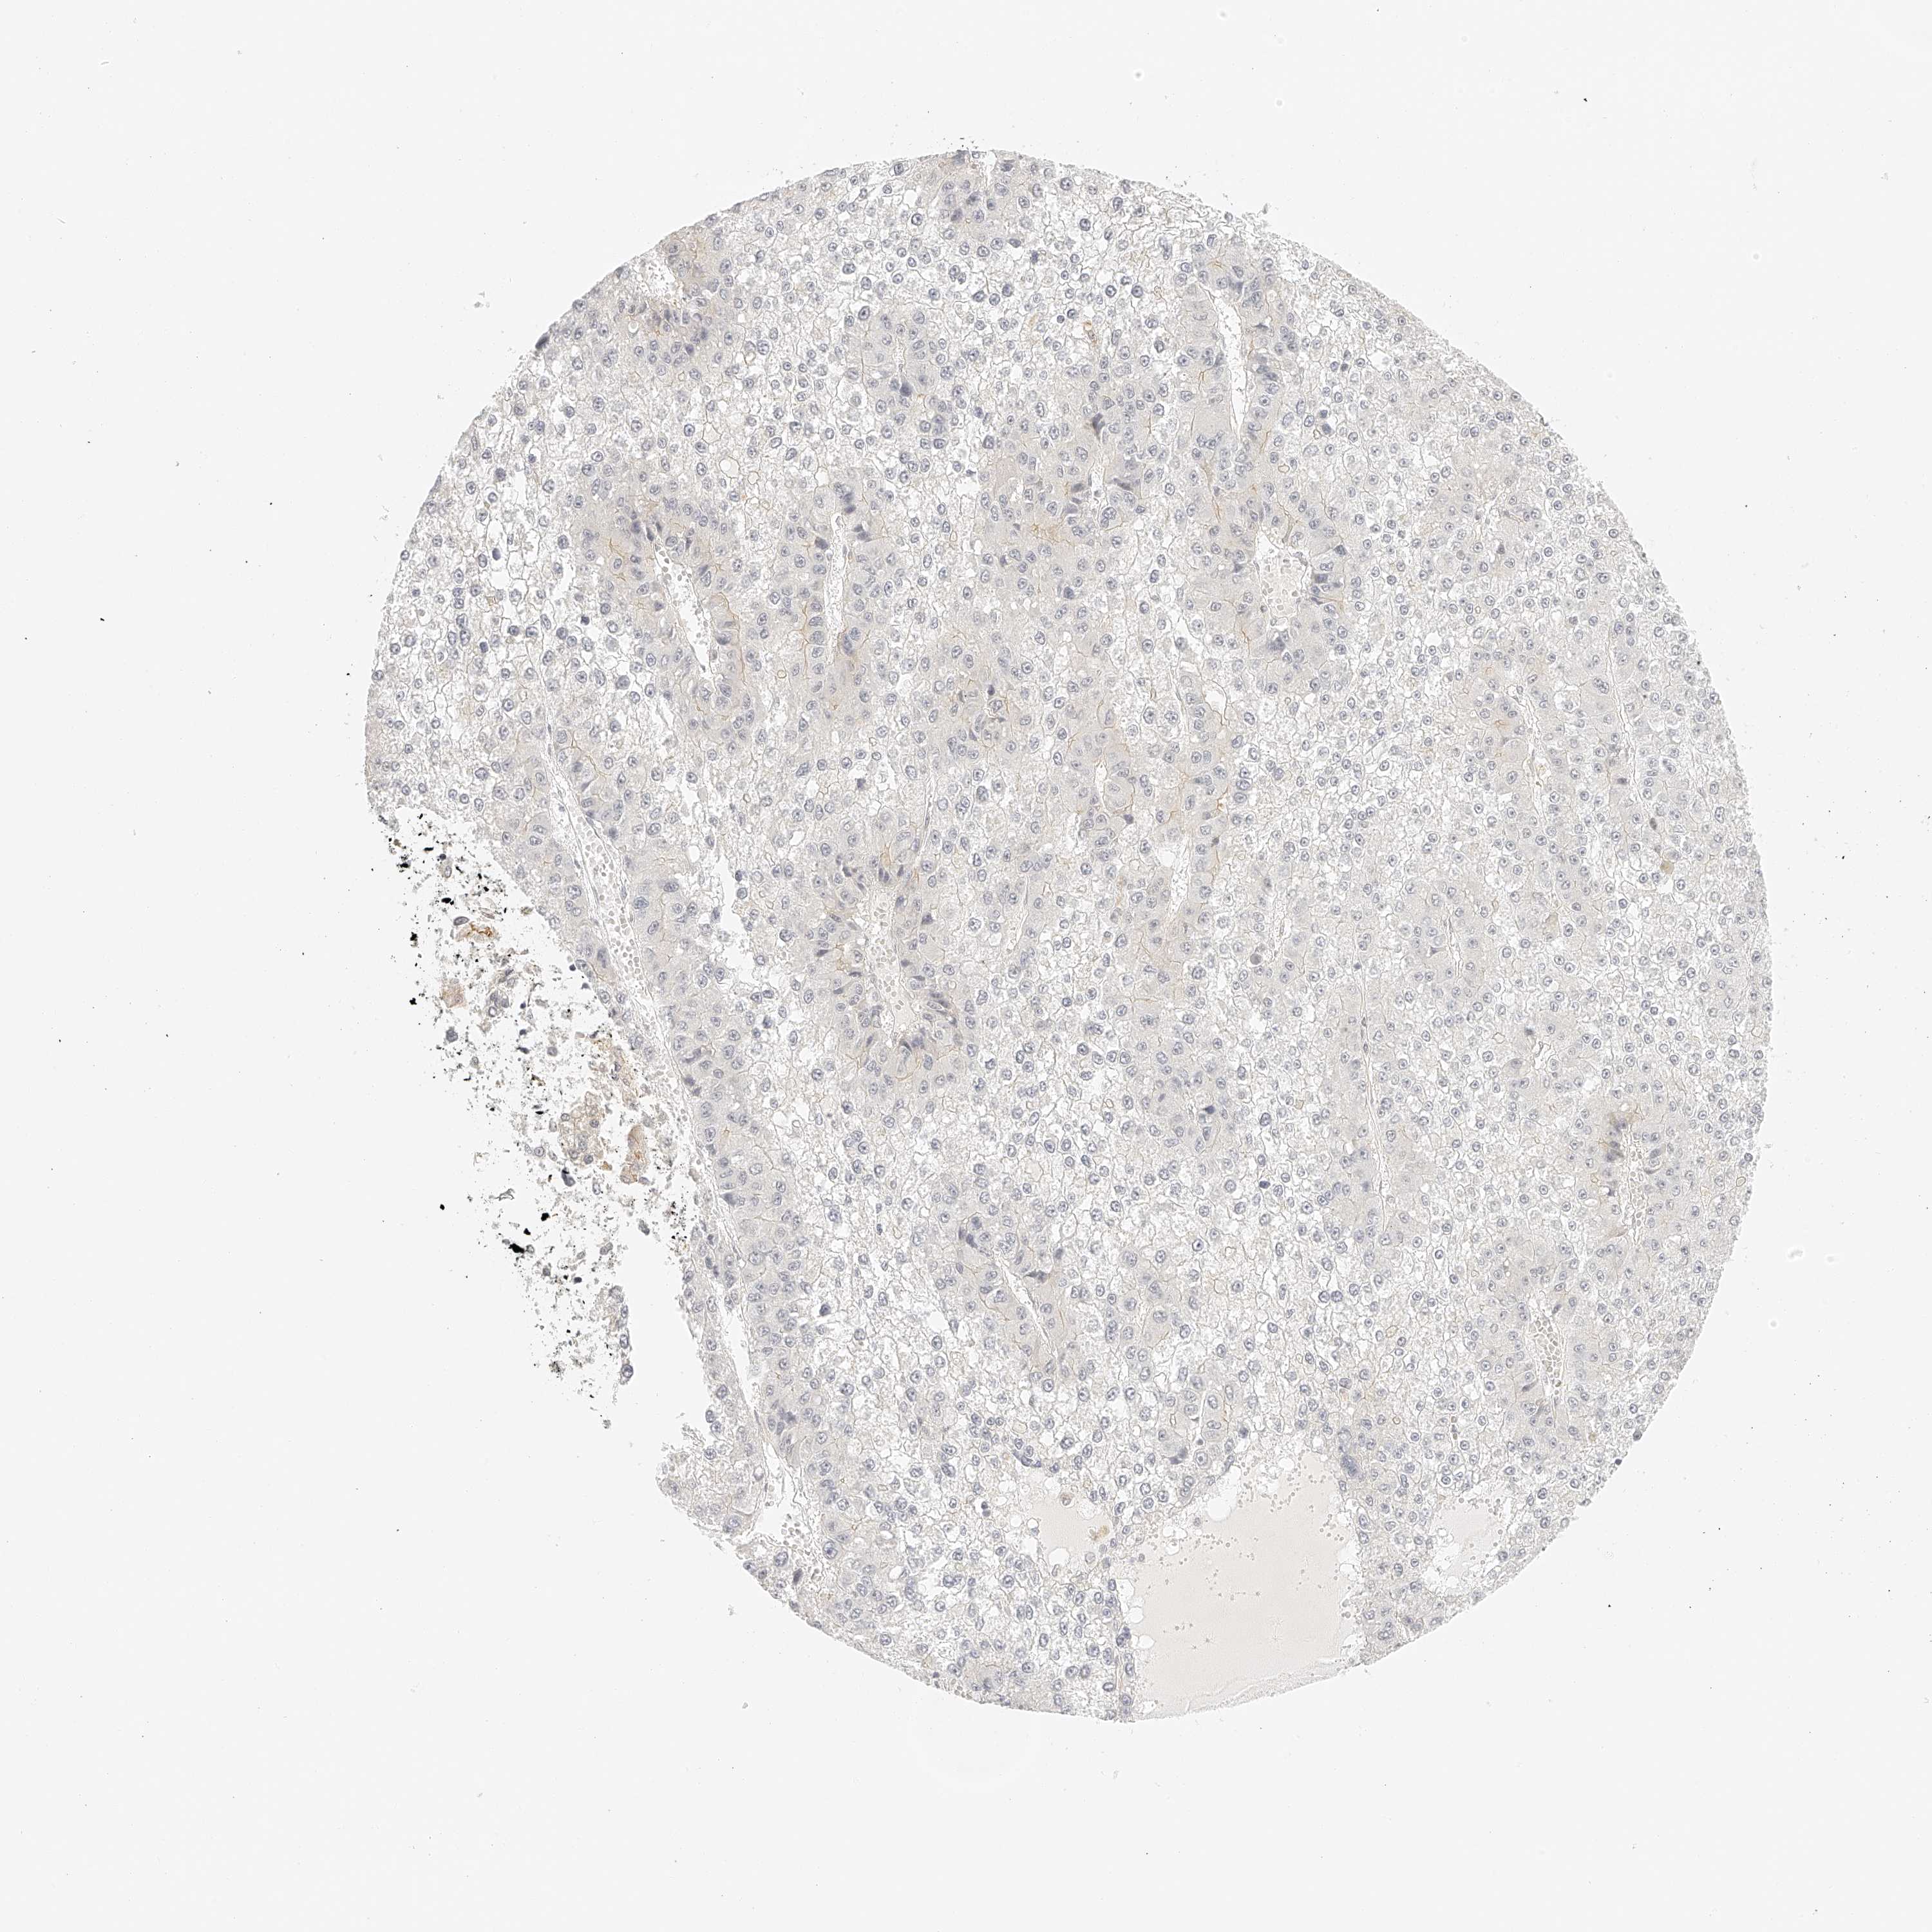

LIVER CANCER - Protein expressioni

A mouse-over function shows sample information and annotation data. Click on an image to view it in a full screen mode. Samples can be filtered based on level of antibody staining by selecting one or several of the following categories: high, medium, low and not detected. The assay and annotation is described here.

Note that samples used for immunohistochemistry by the Human Protein Atlas do not correspond to samples in the TCGA dataset.

Antibody stainingi

Antibody staining in the annotated cell types in the current human tissue is reported as not detected, low, medium, or high, based on conventional immunohistochemistry profiling in selected tissues. This score is based on the combination of the staining intensity and fraction of stained cells.

Each image is clickable and will lead to virtual microscopy that enables deeper exploration of all samples and also displays staining intensity scores, fraction scores and subcellular localization as well as patient and tissue information for each sample.

Antibody HPA027808

Staining

High

Medium

Low

Not detected

Intensity

Strong

Moderate

Weak

Negative

Quantity

>75%

75%-25%

<25%

None

Location

Nuclear

Cytoplasmic/membranous

Cytoplasmic/membranous,nuclear

Cholangiocarcinoma

Carcinoma, Hepatocellular, NOS